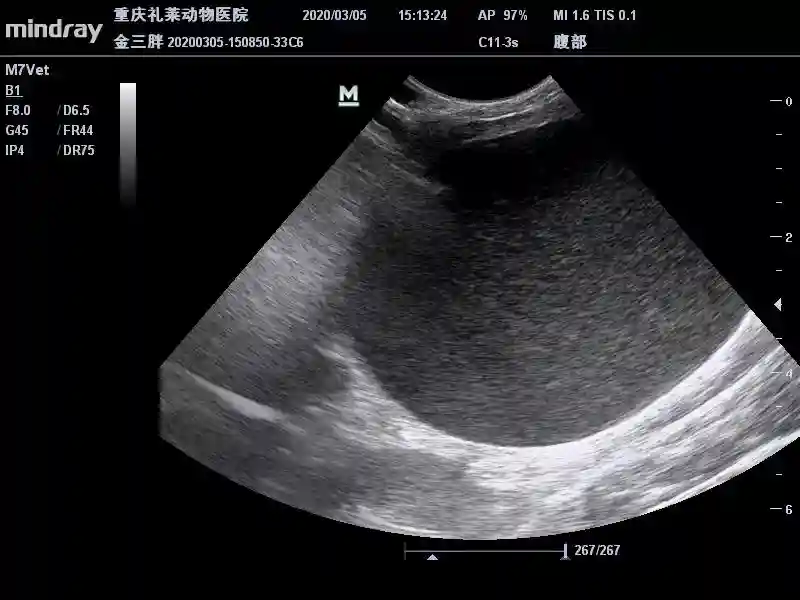

3月23日B超复查膀胱:

膀胱内散在高回声声影减少,膀胱壁光滑。